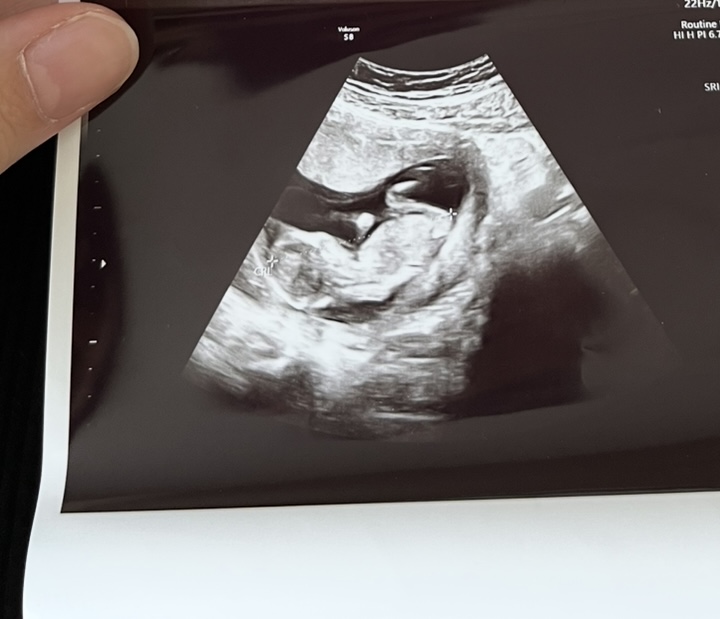

image

benimkine de tahmin yürütebilir misiniz ? Kese şekli vs gibi

Sizinki de kız sanki